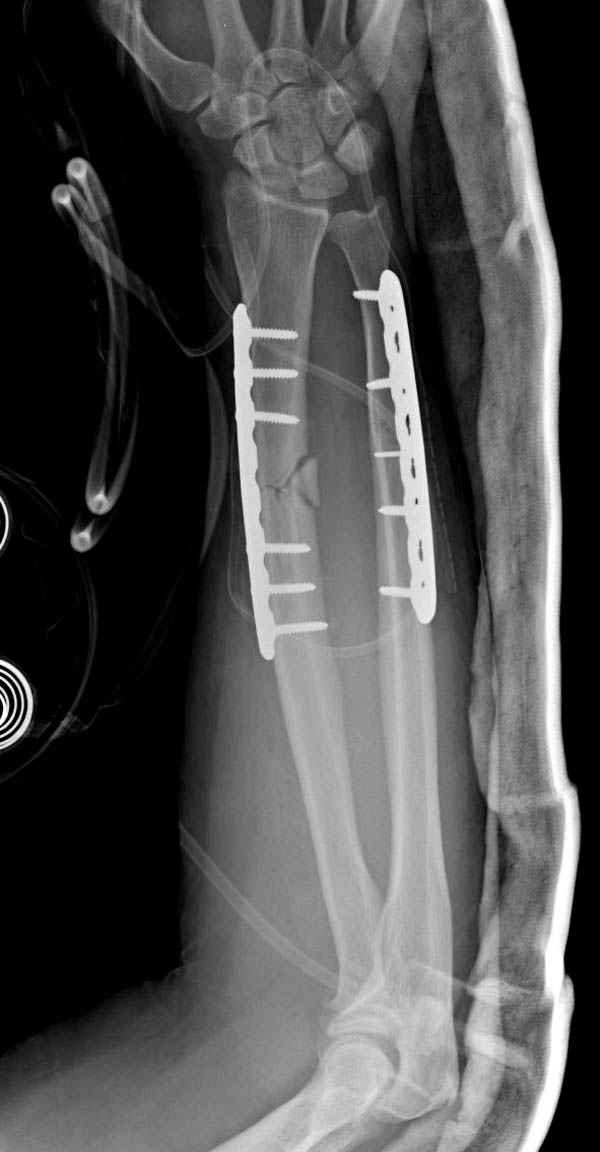

Второй случай, для лечения перелома проксимального

плеча применили пластину "Hand Innovation"

http://www.handinnovations.com/pdf/S3_technique.pdf

Пластина имеет преимущества перед другими "Locking

Implants", потому что пластину можно уложить намного ниже чем другие пластины и имеется возможности проведения шурупов под 130 градусным углом, таким образом можно уменьшить операционный разрез в проксимальной части.

Прооперирован вчера на 13 день после поступления.

Больному 41 и из-за гемодинамической нестабильности в течение первых 7 дней был в реанимации под интубационной седацией.

Кроме перелома плеча у больного старый дистракционный перелом T12-L1 оперированный когда-то и кем-то, открытый перелом костей предплечья, который был прооперирован в ночь поступления, после I&D (хирургической обработки). Из-за разрыва селезенки при поступлении травма хирургами произведено удаление.